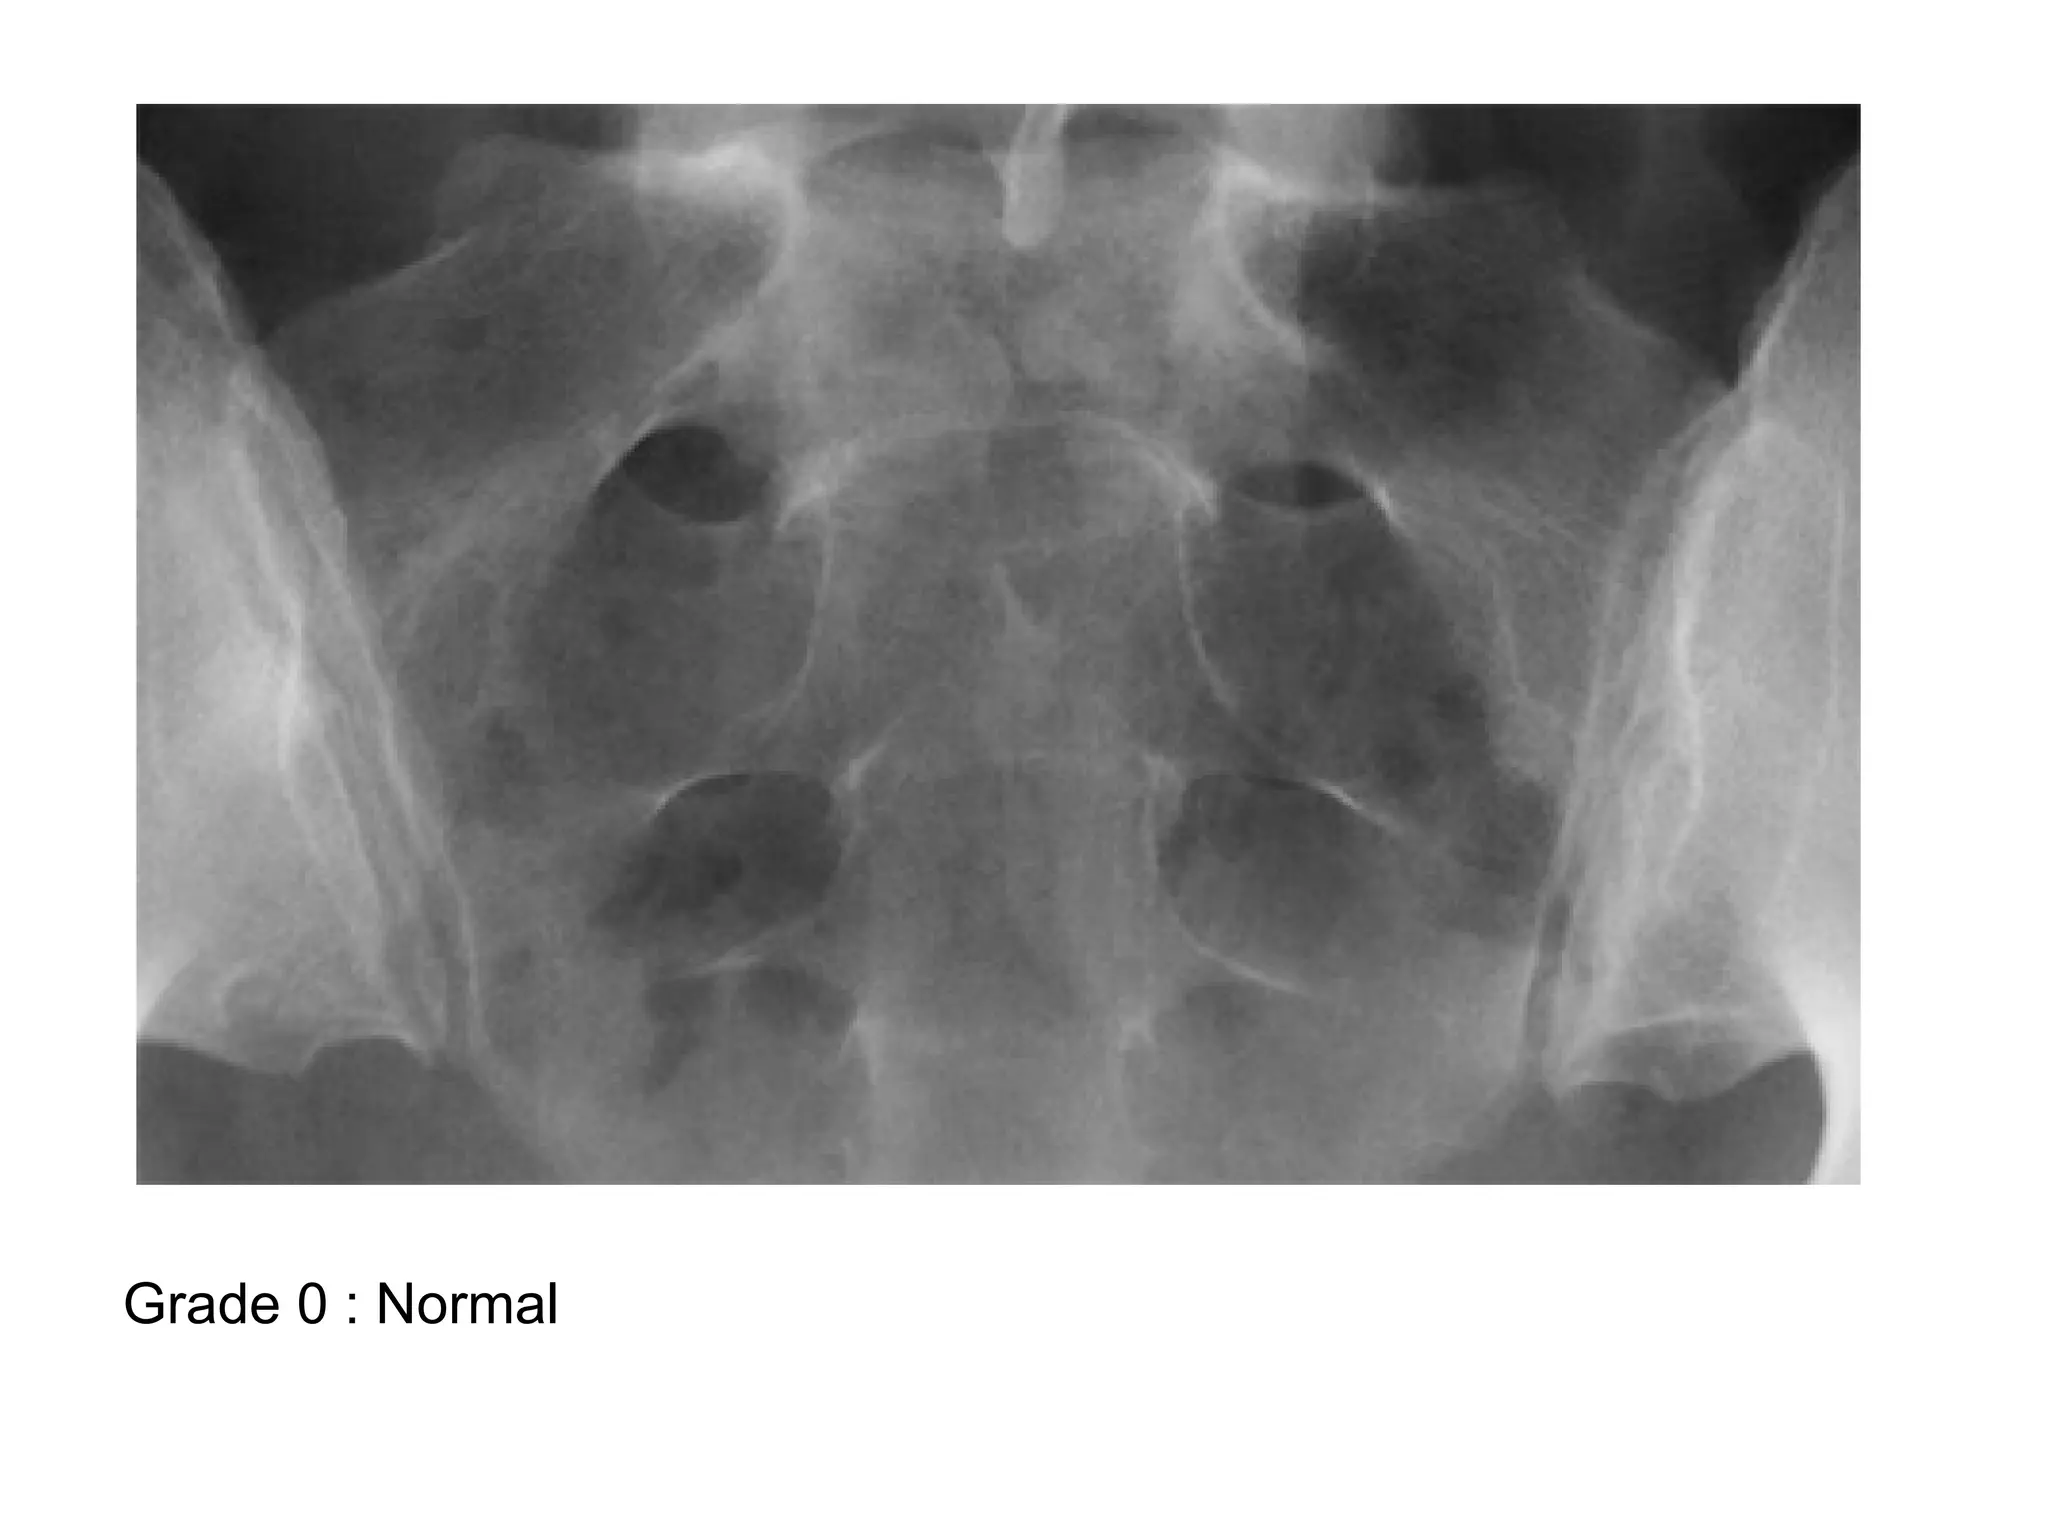

-Grading of Sacroilitis :

*Grade 0 : Normal

Grade 0 : Normal